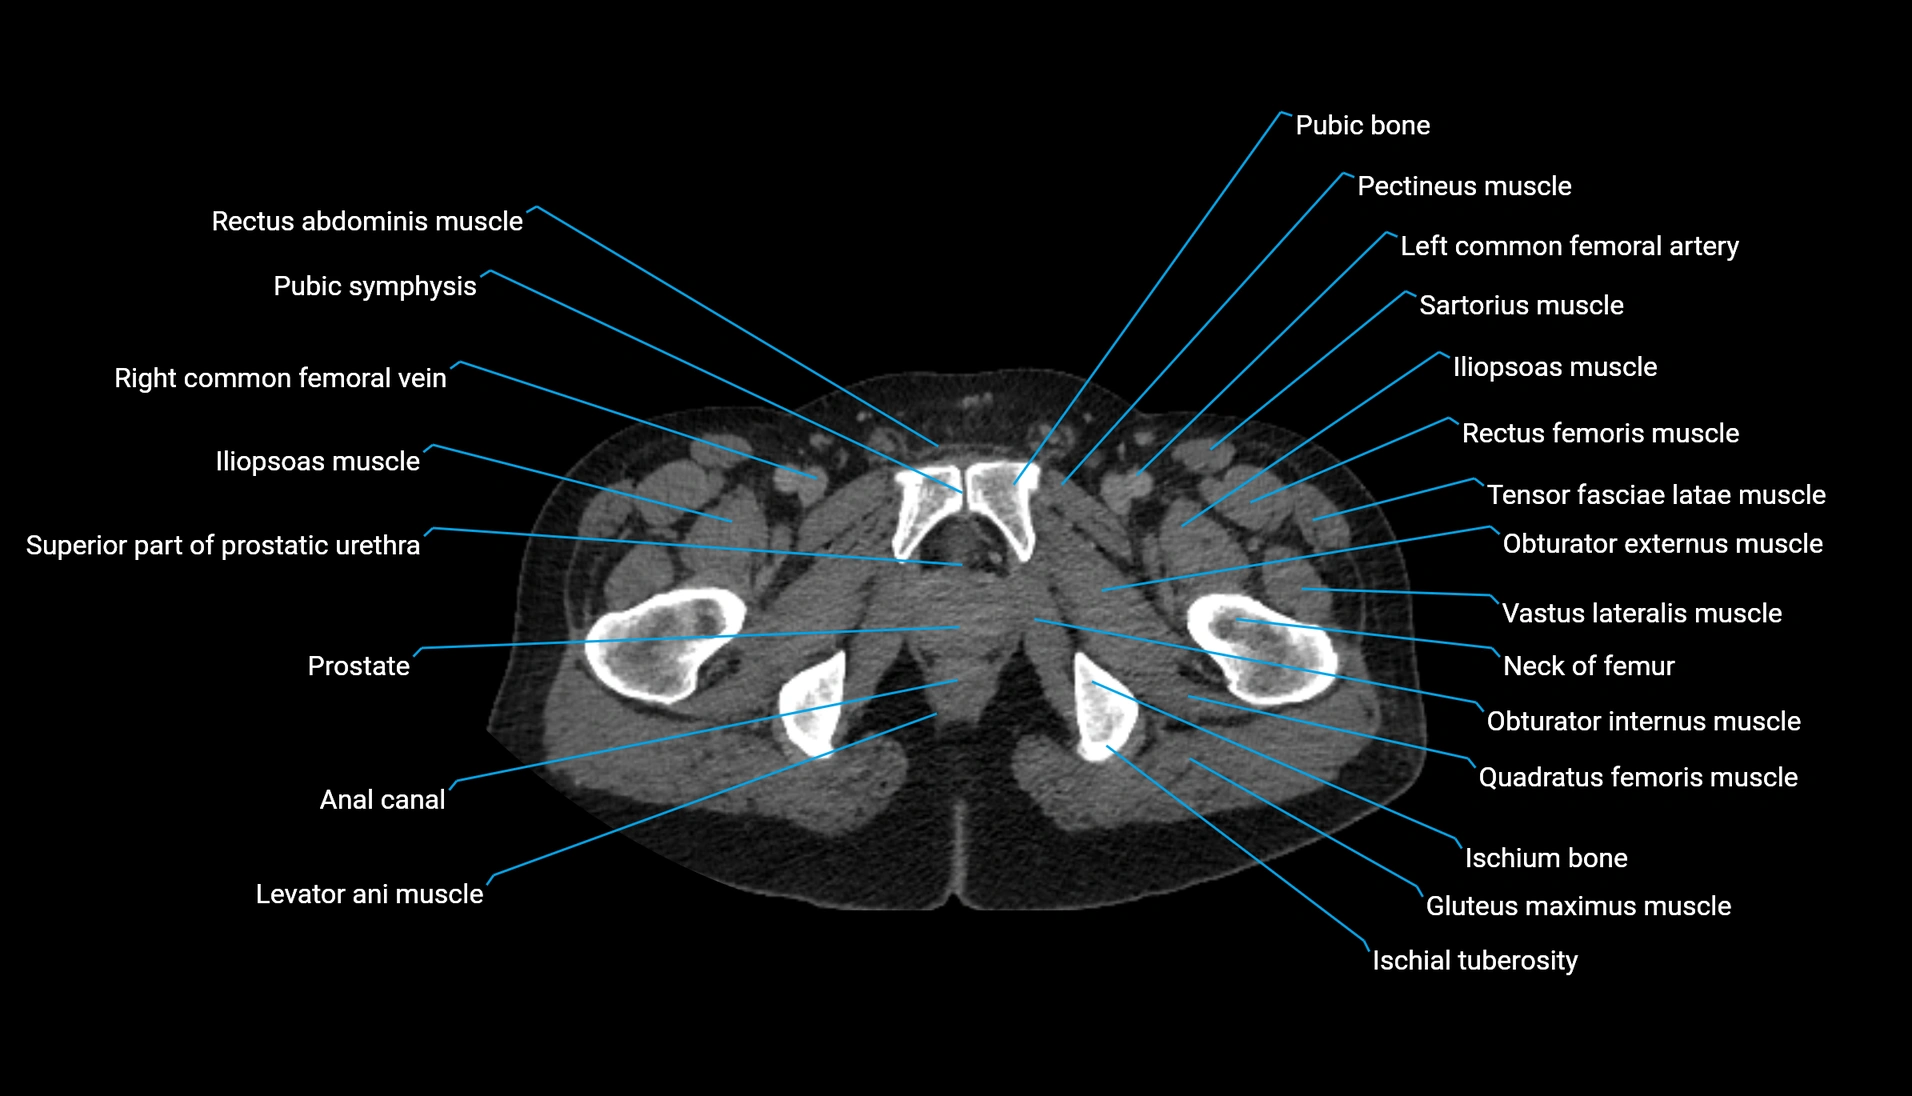

CT Appearance

Non-contrast CT:

-

Demonstrates cortical bone of acetabular rim in excellent detail

Detects fractures, dysplasia, retroversion, or bony overcoverage (pincer impingement)

3D reconstructions used in preoperative hip surgery planning

CT VRT 3D image

CT image